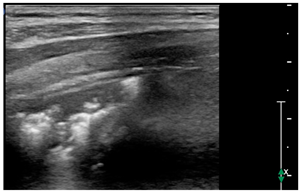

- Subpleural consolidation: Small, triangular, or oval shaped, echo-poor region adjacent to the pleura without a tissue-like pattern (AB)

- Broken pleural line with subpleural consolidations < 1 cm

Subpleural consolidations, on the other side, as well as lobar consolidations, have been described in viral pneumonitis and bronchiolitis, pneumonia, acute respiratory distress syndrome [24], and pulmonary infarction [25], but are not described in cardiogenic pulmonary edema [18].

Subpleural consolidations can also be present in a diffuse microembolic/microthrombotic event. This phenomenon is common in COVID-19 patients [27] because of thrombotic occlusion of small- to mid-sized pulmonary arteries with subsequent infarction of lung parenchyma and can show at LUS a triangular hypoechoic consolidation with sharp margins in the absence of air bronchograms [28].

Our patients showed the presence of subpleural consolidations or consolidations with or without pleural effusion correlating with the degree of heart failure (LVEF at admission and need for inotropes), and this is a new finding. Subpleural consolidations are common in COVID-19 pneumonia in children [8] and have also been described in asymptomatic pediatric patients [30,31]. It is possible that this pattern in MIS-C patients refers to sequelae of the primary infection that had not been detected during initial SARS-CoV-2 infection but was still present at time of MIS-C diagnosis. It is also possible that they are expressions of the inflammatory state that these patients show through fever and elevated markers of inflammation [32]. The correlation of subpleural consolidations with PICU length of stay could also be interpreted under this light as a sign of a more severe disease. MIS-C is a novel entity that follows the primary infection with COVID-19 in children which is still under investigation under different aspects. The inflammatory state in this disease seems caused from a cytokine storm that causes fever, elevation of all markers of inflammation and multiorgan failure, with activation of T cells, macrophages, natural killer cells and overproduction of immune or non-immune defense cells, and the release inflammatory cytokines and chemical mediators. Endothelial cell dysfunction follows, resulting in damage to the microvascular system and abnormal activation of the coagulation system, resulting in systemic small vessel vasculitis and extensive microthrombosis [33]. Therefore, it is possible to speculate that the pattern we found on LUS is a possible expression of a mix of pathological events on the lung parenchyma, a consequence of both the cardiogenic edema and a direct inflammatory/micro-embolic lung disease.